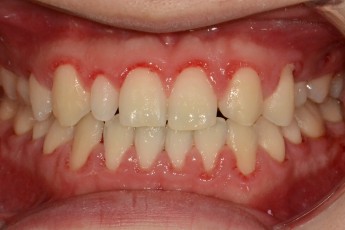

Before

After